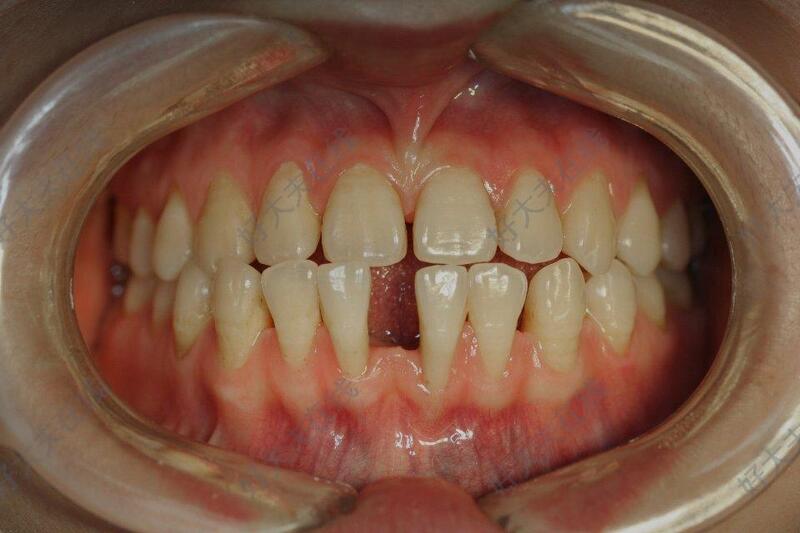

治疗前

牙齿大量散隙,影响美观,影响咬合。近期牙缝越来越大,要求牙齿矫正。